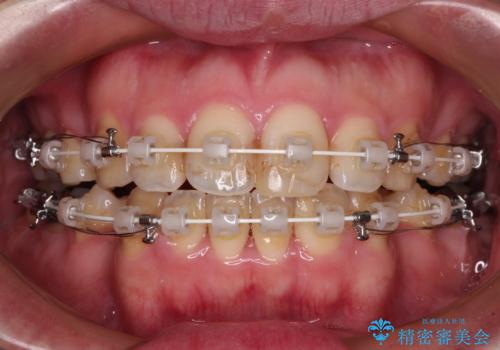

- 矯正装置

- 審美装置

- 治療期間

- 2年6ヶ月

- 治療回数

- 30回以上